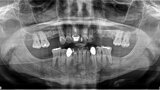

Fig. 5: Pre-op panoramic view.